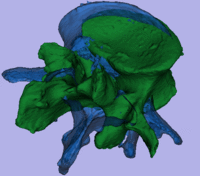

Registration Results

original unregistered unregistered

registered modelsregistered models surface registration